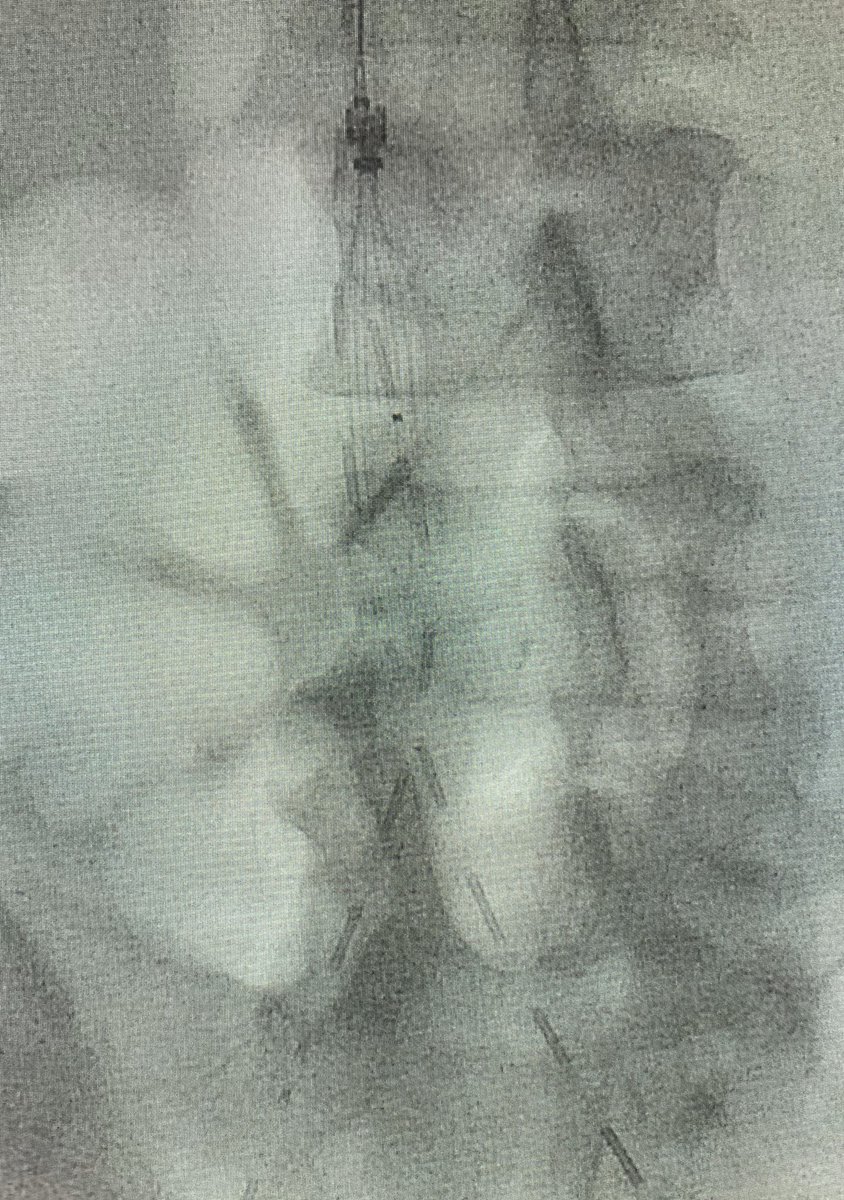

Last case of 2019. Successful

#recanalisation of chronic#splenicvein#occlusion using#transhepatic approach.#portalvein and#SMV reconstructed for#palliation#pancreaticcancer. Wish everyone happy 2020.#irad@SIRspecialists@SIR_ECS@SIRRFS@JVIRmedia@CVIR_Journalpic.twitter.com/Lgma0lTJUd